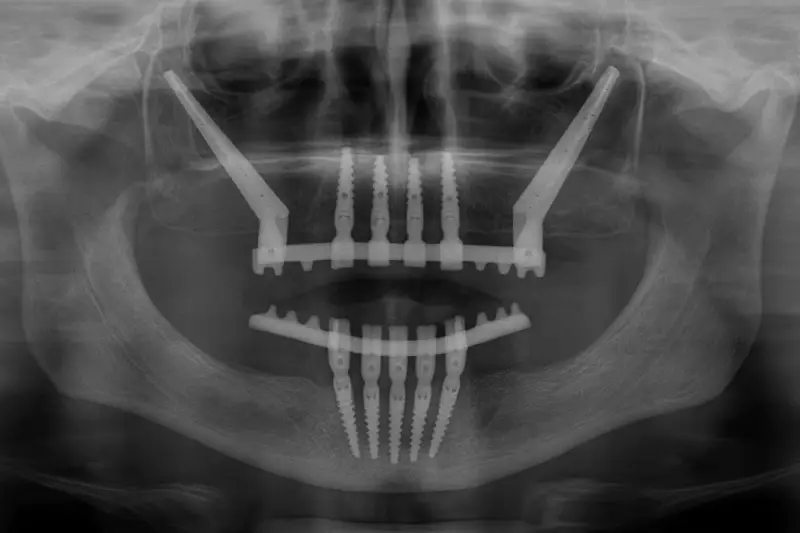

impianti zigomatici albania

Il percorso con impianti zigomatici in Albania segue alcune fasi principali.

• Inserimento degli impianti zigomatici nell’osso mascellare e zigomatico

• Eventuale combinazione con impianti tradizionali, se presenti aree con osso sufficiente